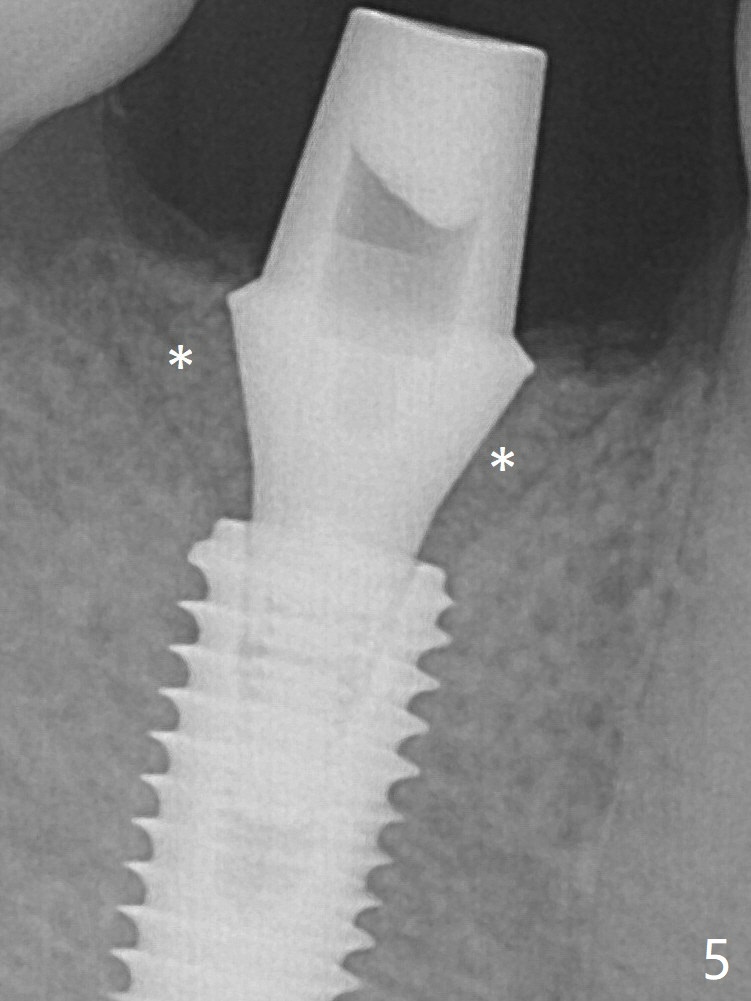

After insertion of a 5.7x5.5(3) mm abutment, Vanilla Graft is placed (Fig.5 * with 2 mm buccal gap). The abutment with a provisional is loose 4 months postop (Fig.6). The abutment screw is loose and fractured 8 and 11 months post cementation, respectively (Fig.7). The fractured screw seems to be loose within the implant well and is easily re-winded out.